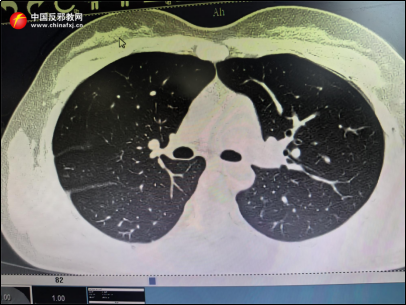

▲22岁健康女性胸部CT